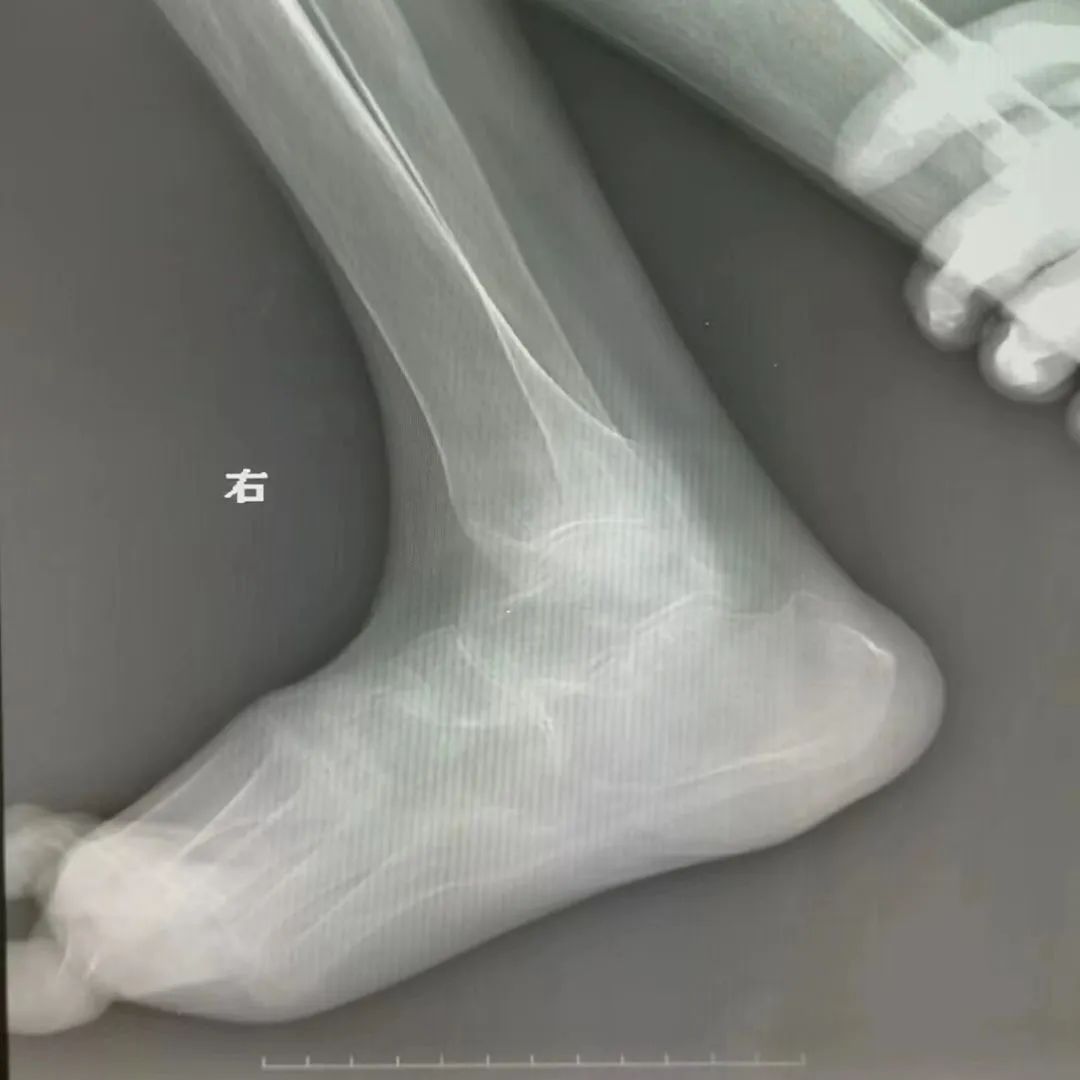

该患者伴有严重的类风湿性关节炎并肢体畸形